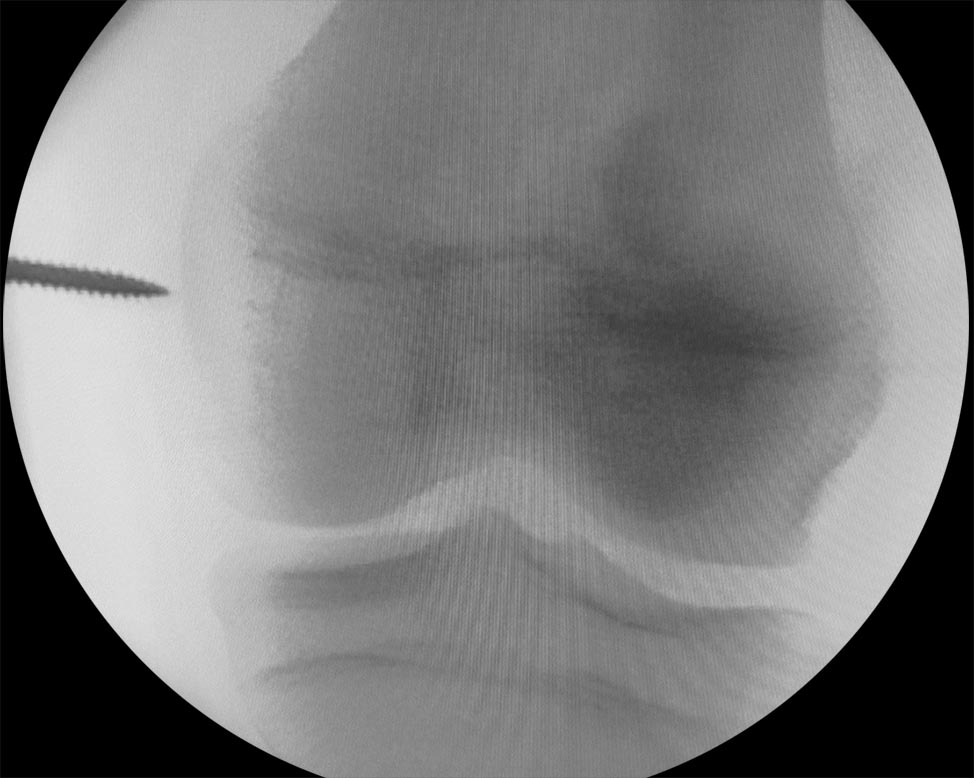

Se toma un injerto del tendón cuadricipital (TC) de espesor completo dejando un margen de 2-3 mm en la zona medial, para permitir un cierre del defecto tendón-tendón. Es importante evitar abrir la cápsula articular. Para ello es conveniente comenzar la disección aproximadamente 3 cm proximal al polo superior de la rótula donde el tendón se encuentra bien diferenciado de la cápsula articular, y luego continuar hacia proximal (Fig. 3). Finalmente se continúa hacia distal con una disección subperióstica hasta la inserción anatómica del LPFM en la rótula. Este gesto permite ganar 1-1.5 cm de longitud final del injerto. Se mantiene la inserción rotuliana del TC y se lo gira sobre sí mismo de modo que la cara posterior quede anterior y viceversa. Se fija el extremo distal del tendón con puntos tipo Krakow y se refuerza la inserción rotuliana con puntos en 8, ambos con suturas no absorbibles tipo Fiberwire. Se diseca el plano entre vasto medial oblicuo (VMO) y el retináculo medial. Se identifica con el arco en C, en un perfil estricto, el punto anatómico de inserción femoral del LPFM. Este paso es crítico al momento de la reconstrucción. En pacientes esqueléticamente maduros utilizamos el punto de referencia radiográfico descripto por Schöttle.7 En pacientes esqueléticamente inmaduros fijamos el injerto en la región epifisaria inmediatamente distal al cartílago de crecimiento (Fig. 4), ya que este punto de referencia no es fiable en pacientes con fisis abierta.8

Figura 4: Imagen de frente y perfil donde se identifica el punto de inserción femoral con arco en C en un paciente esqueléticamente inmaduro. Nótese la posición inmediatamente distal a la fisis en el frente y alineada con la cortical posterior del fémur en el perfil